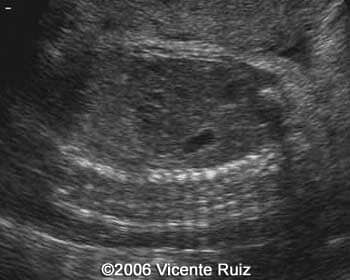

Axial views of the chest showing the left hemithorax occupied by an heterogeneous mass

Note the stomach into the left hemithorax